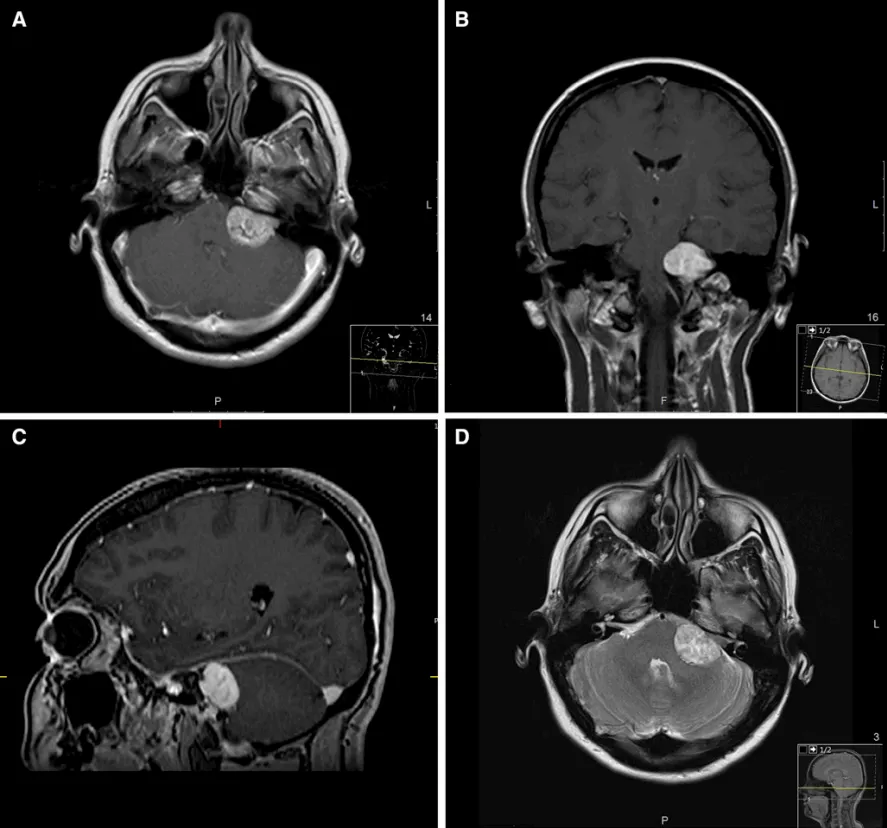

正值壮年的阿宇,右耳突发刺痛并急剧失聪,同时伴有面部与舌部麻木。起初他被误诊为"噪音性耳聋",接受相应治疗却毫无起色,症状反而愈演愈烈。进一步检查后真相大白——他患的是19.8×28mm的大型听神经瘤,肿瘤已重压小脑与脑干,随时可能引发更严重的神经损害。

听神经瘤的危害绝不止于表面症状,除耳鸣、面瘫、表情失控等"面子"困扰外,随着瘤体持续增大,还会压迫脑干,引发头晕呕吐、吞咽困难,乃至危及生命。桥小脑角区神经血管交错密布,手术难度极高,阿宇几经辗转难觅满意方案,最终找到擅长脑干及CPA区复杂手术的巴特朗菲教授。

凭借精湛的显微外科技术,巴教授为阿宇实现了肿瘤完整全切,同时完好保留了面神经与听神经的解剖结构和功能。术后仅出现轻度面瘫,属面神经正常水肿反应,经规范康复训练后半年内基本恢复,听力与面部功能均达到良好状态,彻底摆脱了肿瘤困扰。